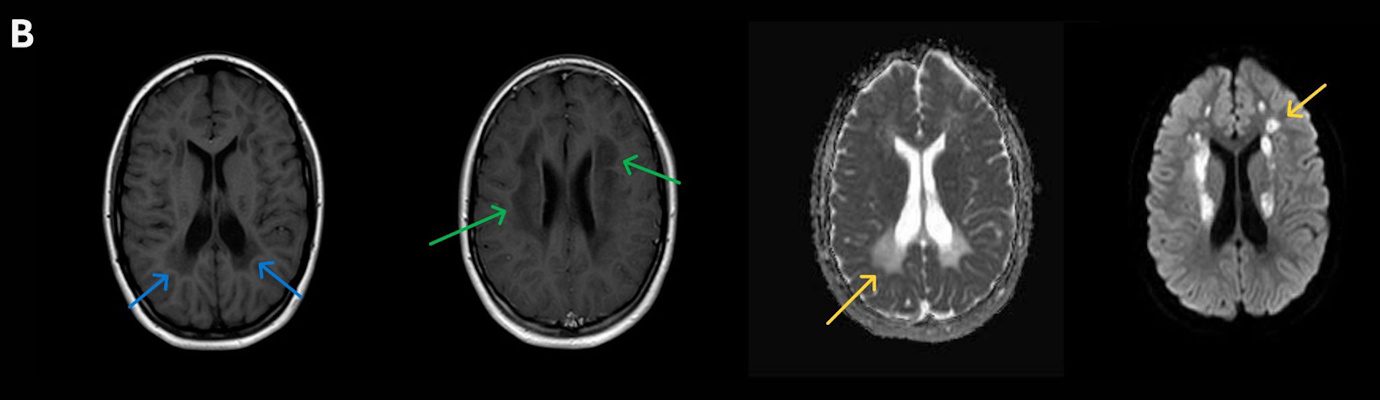

- B) Kontrastsız T1A serilerde tarifli alanlarda hipointens (oklar) görünüm izlendi. Kontrastlı T1A serilerde bu düzeyde (oklar) kontrastlanma artışı izlenmedi. Diffüzyon ağırlıklı serilerde belirgin diffüzyon kısıtlaması (oklar) görülmedi.

- LBSL, karakteristik radyolojik özelliklere sahiptir. MRG’de tipik olarak bilateral ve simetrik beyaz cevher sinyal değişiklikleri görülürken, subkortikal U lifleri, internal kapsülün posterior kolları, trigeminal sinir traktları, serebellum, korpus kallozumun spleniumu, medulla oblongata ve omurilikteki dorsal kolonlar ile lateral kortikospinal traktlar genellikle korunur.

- Etkilenen bölgelerde T1’de hipointens, T2/FLAIR’da hiperintens sinyal değişiklikleri izlenir. DWI’de lezyonların periferinde kısıtlı difüzyon görülebilir. MRS’de beyaz cevherde laktat artışı saptanabilir, ancak bu her hastada mevcut değildir.

- LBSL tanısında majör kriterler; subkortikal U lifleri korunmuş serebral beyaz cevher, servikal düzey dahil omurilik dorsal kolonları ve lateral kortikospinal traktlar, medulla oblongata piramitleri veya medial lemniskus dekusasyonu tutulumu iken; minör kriterler korpus kallozum spleniumu, internal kapsül posterior kolu, superior ve inferior serebellar pedinküller, trigeminal sinir traktları, mezensefalik trigeminal yollar, medulla oblongata anterior spinosebellar traktları ve serebellar beyaz cevherdeki sinyal değişiklikleridir.